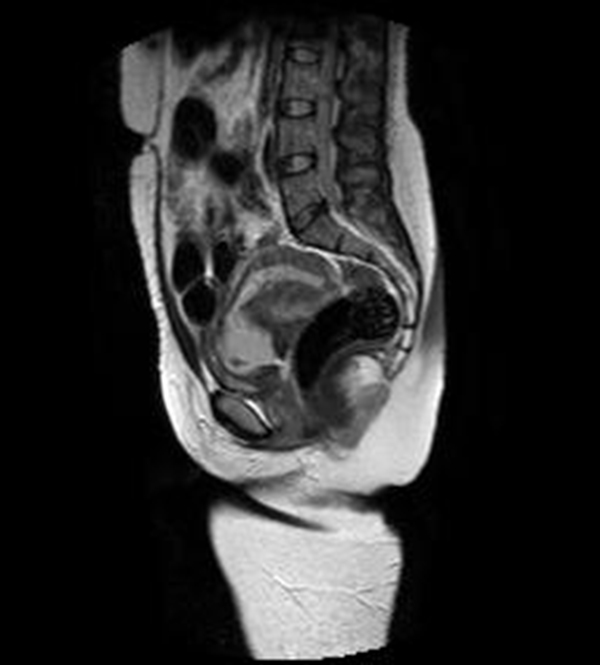

Se realizó una RNM (Philips 1.5 Tesla) que permitió confirmar el diagnóstico de EEC (figuras 5 a 8).

El propósito de la RMN es aportar información adicional para mujeres que necesiten un diagnóstico preciso, caracterización del tejido y ubicación espacial. Algunas indicaciones de la resonancia en el EE son las complicaciones asociadas, hallazgos ecográficos no concluyentes o complicaciones del EE, como las localizaciones abdominal, intersticial, miometrial o cervical (26).

La localización cervical de un EE por debajo del orificio cervical interno puede confundirse con un aborto espontáneo en curso, con enfermedad trofoblástica, con un pólipo endometrial que protruye por el canal cervical o con una placenta de implantación baja (27).

Jung y cols. (28) encontraron como hallazgos en RMN de EEC una masa mal definida con señales muy heterogéneas en T2, hiperintensidades internas e irregulares en T1, con un anillo circunferencial o parcial de baja intensidad de señal, con realce periférico irregular del componente sólido papilar, acompañado de vacíos de señal de morfología tubular. Esto va en concordancia con lo referido por Tamai y cols. (27), que describen típicamente el EEC como una masa hemorrágica, heterogénea y con realce intenso de los componentes papilares del tejido.

Una secuencia útil en la identificación del hematoma reciente es el T2*, que podría remplazar el uso del gadolinio en esta indicación particular. La sensibilidad del 95 % y la especificidad del 100 % de esta secuencia mejora significativamente el desempeño de la resonancia en el diagnóstico de EE (29).

El uso de gadolinio intravenoso incrementa la especificidad en el diagnóstico de embarazo tubárico, lo que permite diferenciar el realce normal de la trompa de un hematoma reciente. En este caso, este principio nos ayudó a delimitar la afectación decidual y a descartar la presencia de un hematoma asociado (30). La resonancia con gadolinio también se ha utilizado en el seguimiento del tratamiento conservador del EEC (31).